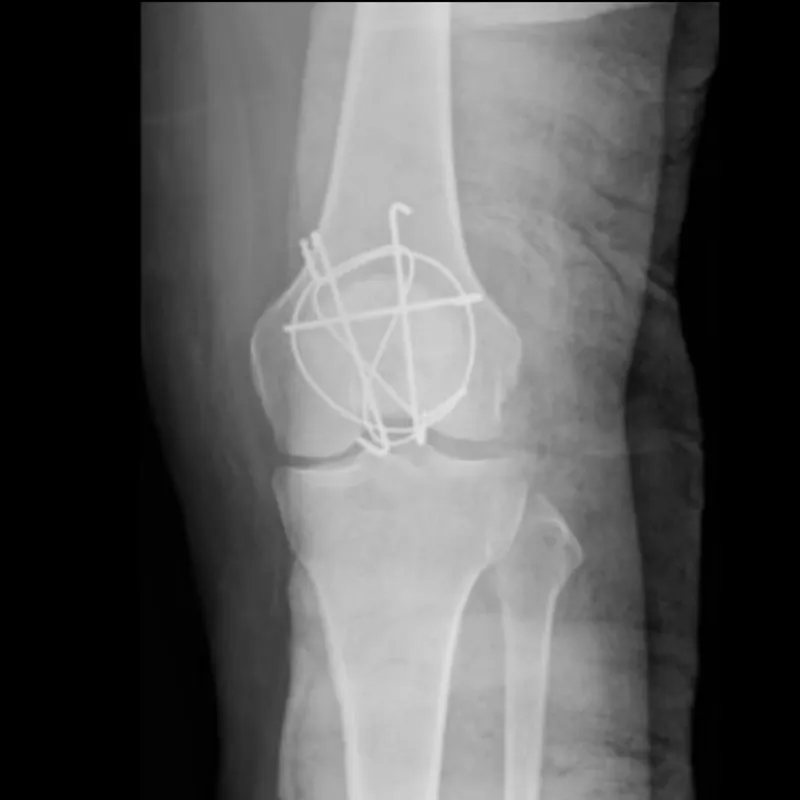

這一跤,

跌斷了左膝的臏骨,與21年的職場生涯。

在我的人生中,慘跌了一跤。